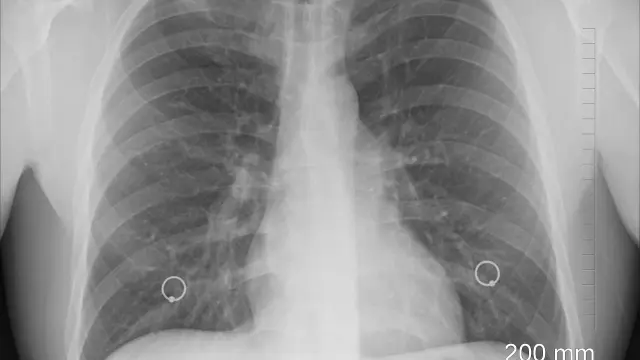

Un sistema de inteligencia artificial (IA) detecta la tuberculosis (TB) en las radiografías de tórax a un nivel comparable al de los radiólogos, según un estudio publicado en 'Radiology', revista de la Sociedad Radiológica de Norteamérica (RSNA). Los investigadores afirman que el sistema podría ayudar a la detección en zonas con recursos limitados de radiólogos.

Kazemzadeh y sus colegas desarrollaron y evaluaron un sistema de IA que puede evaluar rápida y automáticamente las radiografías de tórax para detectar la tuberculosis. El sistema utiliza el aprendizaje profundo, un tipo de IA que puede aplicarse para enseñar al ordenador a reconocer y predecir condiciones médicas.

Los investigadores desarrollaron el sistema utilizando datos de nueve países. Luego lo probaron con datos de cinco países, cubriendo múltiples países con alta carga de TB, varios entornos clínicos y una amplia gama de razas y etnias. Se utilizaron más de 165.000 imágenes de más de 22.000 pacientes para desarrollar y probar el modelo.

El análisis con 14 radiólogos internacionales mostró que el método de aprendizaje profundo era comparable al de los radiólogos para la determinación de la TB activa en las radiografías de tórax.